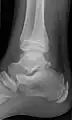

Os trigonum

The os trigonum or accessory talus represents a failure of fusion of the lateral tubercle of the posterior process of the talus bone. Is estimated to be present in 7–25% of adults.[17] It can be mistaken for an avulsion fracture of lateral tubercle of talus (Shepherd fracture) or a fracture of the Stieda process. In most cases, Os Trigonum will go unnoticed, but with some ankle injuries it can get trapped between the heel and ankle bones which irritates the surrounding structures, leading to Os Trigonum Syndrome.[21]